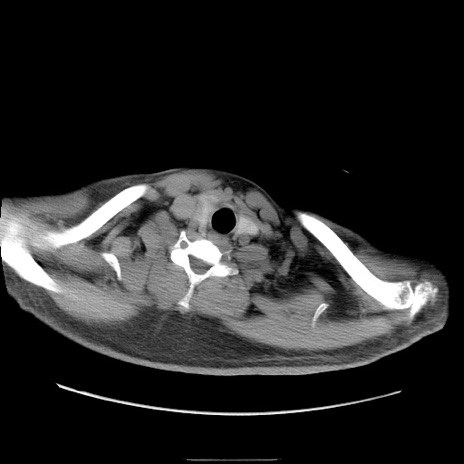

冠状断像